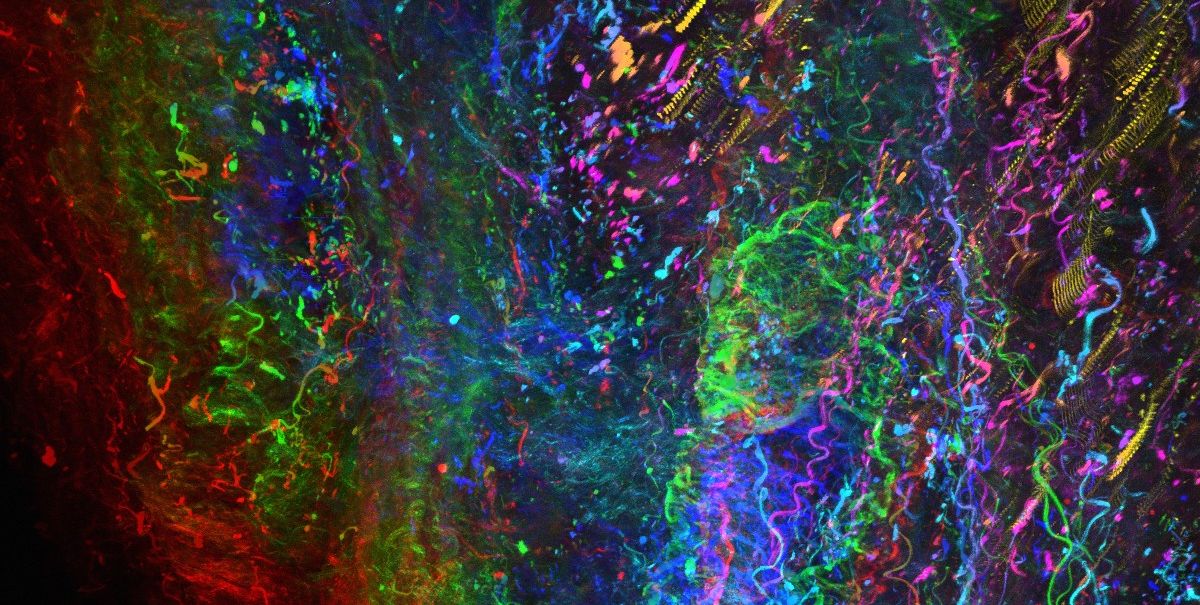

A dnes už vím, že některé vlastnosti nádoru mohou léčebnou účinnost nanočástic ovlivnit. Třeba nadměrný extracelulární matrix, tedy mimobuněčná hmota, která se nachází mezi buňkami tkání. V místě nádoru může tedy fungovat jako fyzická bariéra, která brání pronikání léčiva. Chci studovat, jak nanočástice s různými složkami nádorového mikroprostředí interagují. Projekt, na kterém teď pracuji, by měl identifikovat vlastnosti nanočástic, které umožní lepší průnik, a tím pádem účinnější distribuci léčiva. Věnuji se léčbě zaměřené přímo na extracelulární matrix a jeho hlavní producenty – fibroblasty.

Nejjednodušeji se nanočástice pozorují pomocí fluorescenčního značení. Pokud zbarvíme jejich povrch nebo vnitřek, můžeme sledovat jejich pohyb uvnitř buněk nebo uvnitř tkání laboratorních myší.

Tady na stáži na University of Melbourne se nezaměřujeme jen na rakovinu. Zkoumáme třeba i distribuci inzulínu při cukrovce. Já osobně jsem pracovala především s nádory tlustého střeva, prsu a na ICRC jsem se věnovala nádorům prostaty. V Brně jsme vytvořili organoidní model, na kterém jsme studovali vývoj onemocnění a intenzivně jsme spolupracovali s klinickými lékaři.

Co se týče vědecké práce, chci popsat, jak nanočástice interagují s mikroprostředím nádoru a popsat konkrétní vlastnosti, které by měly mít, aby se nezdržovaly ve fibrózním extracelulárním matrixu a mohly efektivně proniknout do nádoru a ničit tak rakovinné buňky. Případně zjistit, jakým způsobem modulovat extracelulární matrix. Tady v Melbourne mám k dispozici materiálovou expertizu a v Brně organoidní modely a pacientské tkáně, můžu to tak testovat přímo na nich, to je obrovský krok kupředu.